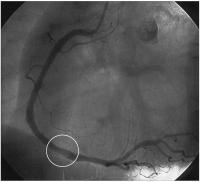

Mobiler Thrombus in der RCA bei NSTEMI

Abbildung 3: Angiogramm der rechten Koronararterie: diffuse nichtstenosierende sklerotische Veränderungen; Kontrastmittelübertragungsdefekt im mittleren Drittel (Kreis).